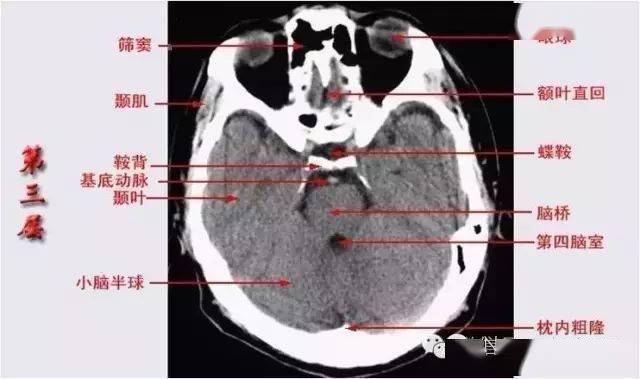

1,颅底层面:前半主要显示眼球,眼外肌,视神经,筛窦